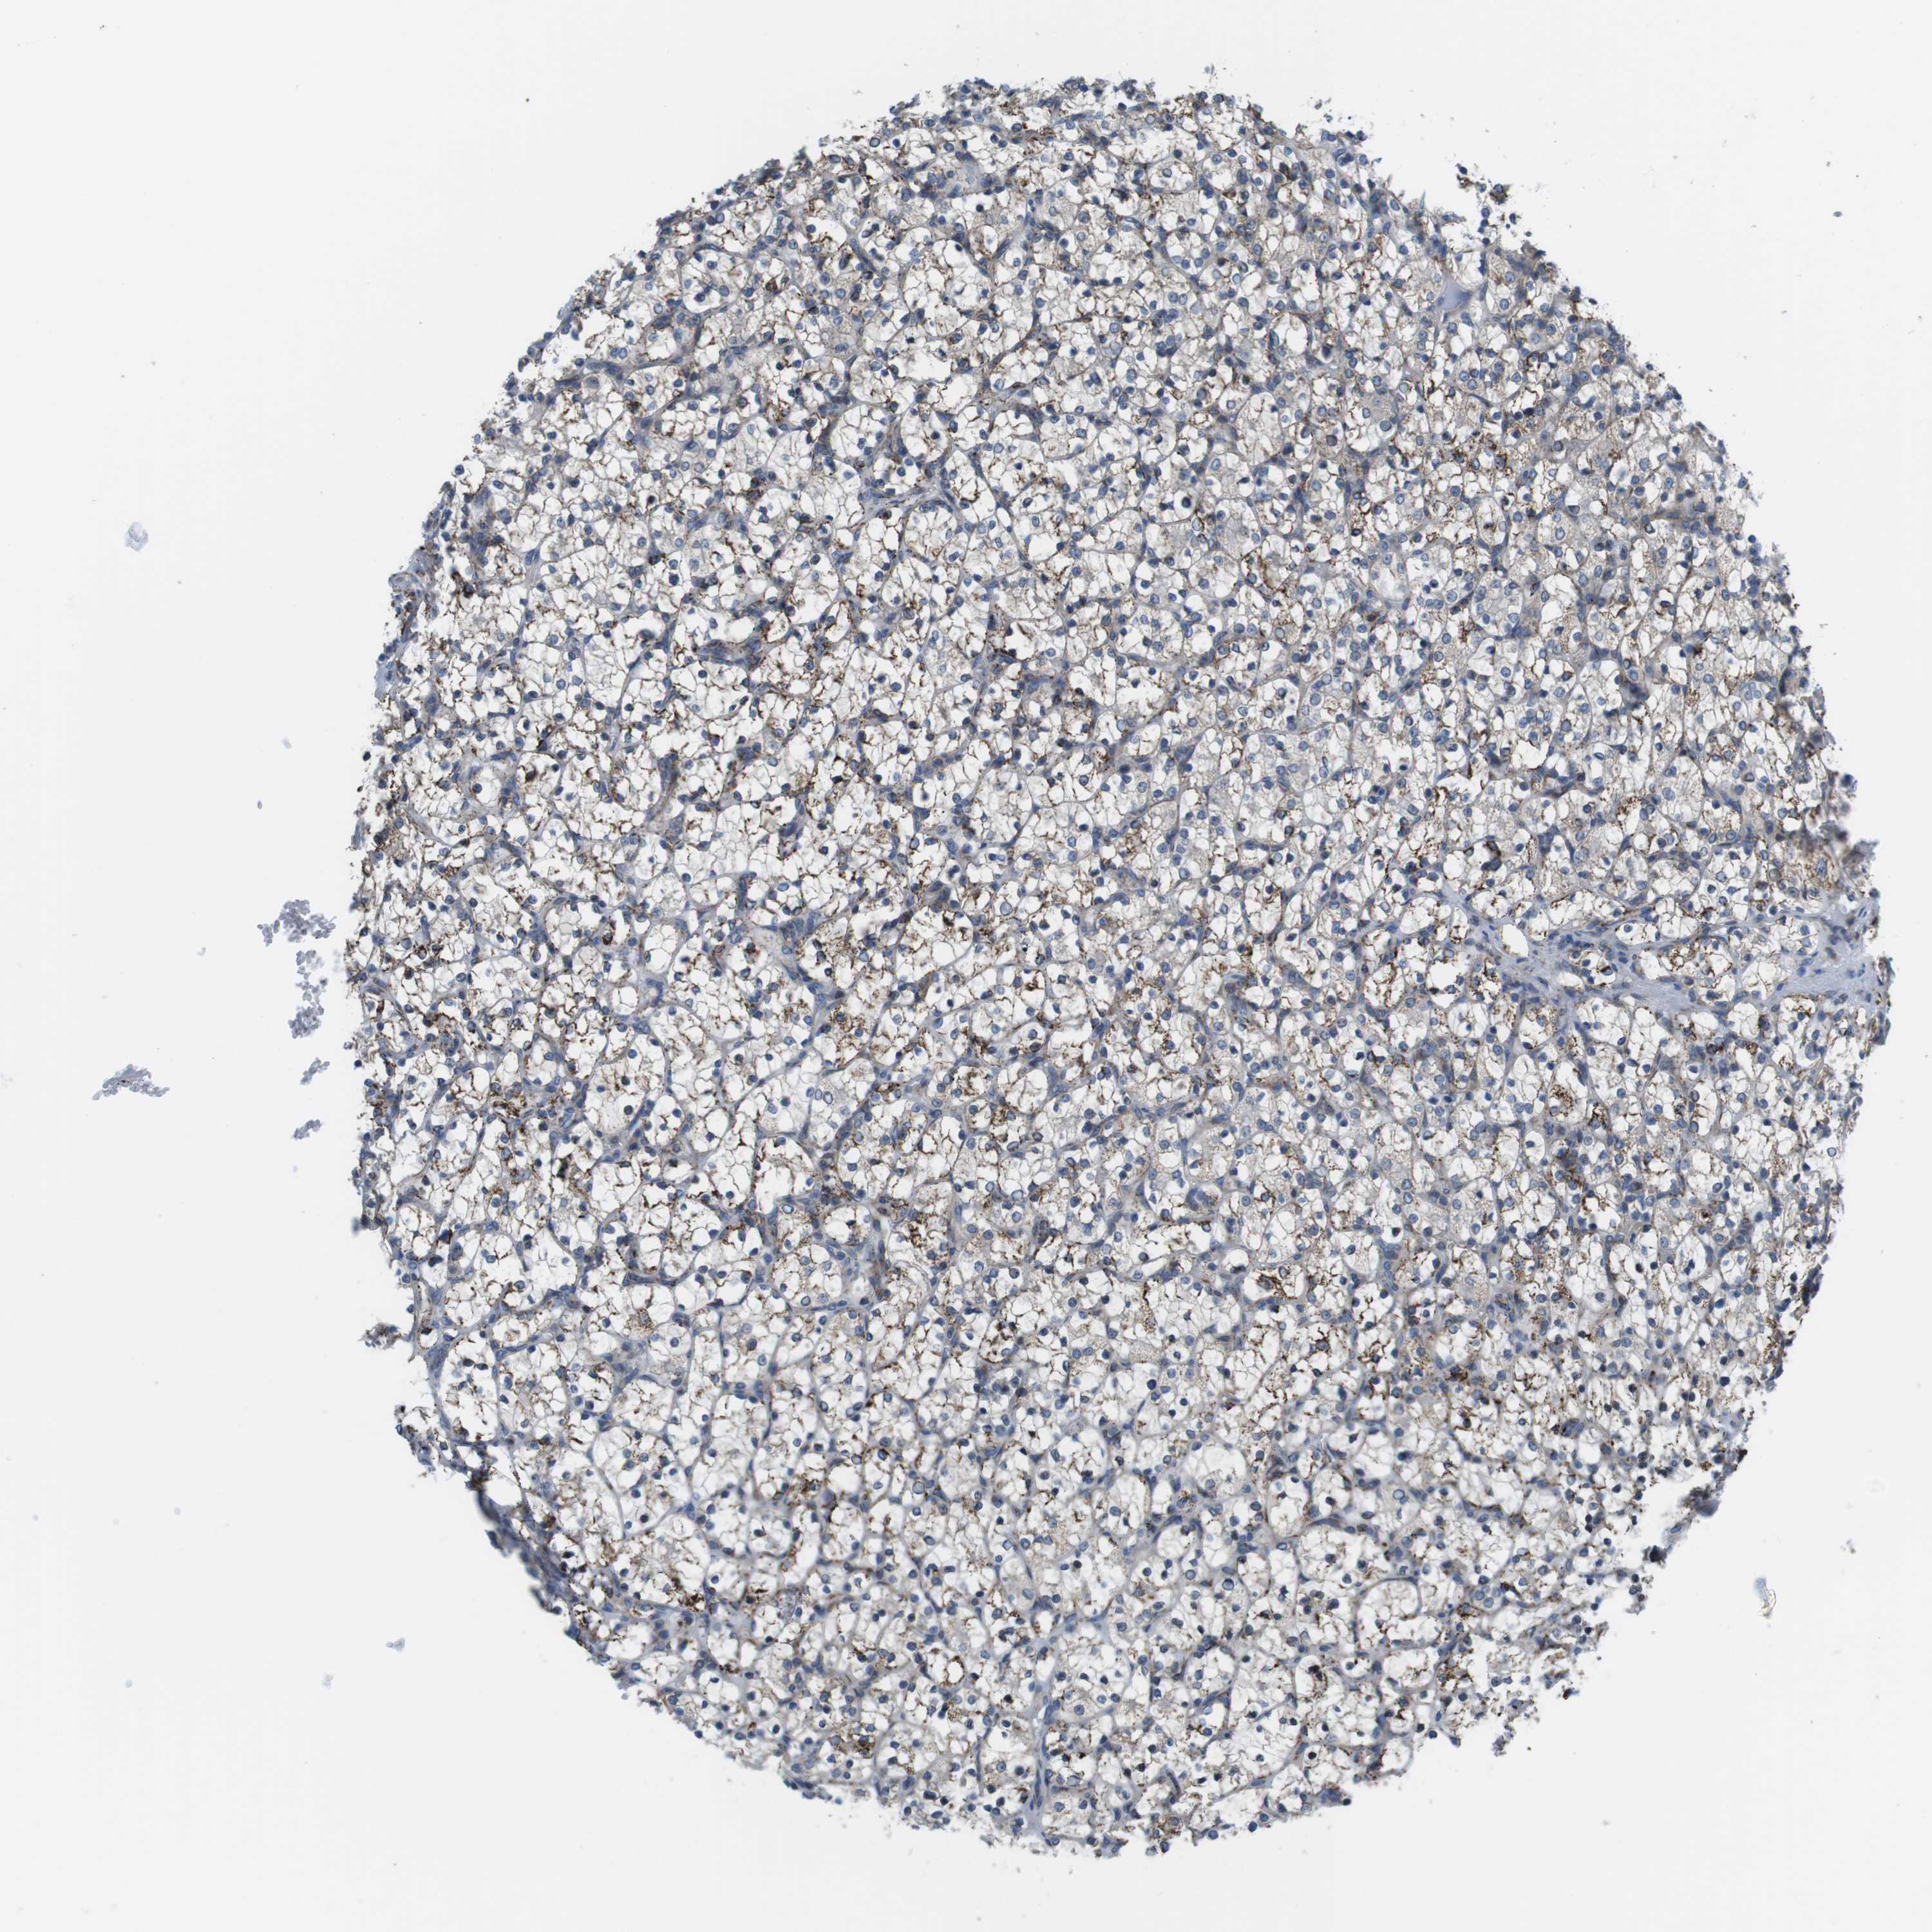

Average pTPM 69.8

Number of samples 521